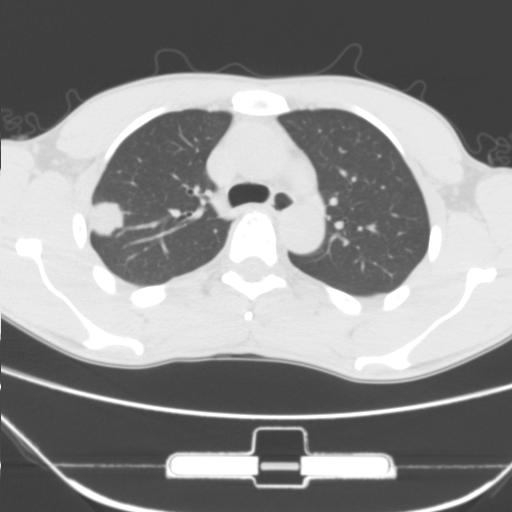

右肺上叶后段近胸膜下结节样异常密度灶,似见分页及毛刺,考虑右肺上叶周围型肺ca,建议穿刺病理检查

缺乏病史,症状体征,但这个孤立结节具备了几乎所有的恶性征象:分叶,毛刺,空泡征,胸膜凹陷征,血管集束。

考虑右肺上叶后段周围型肺癌。